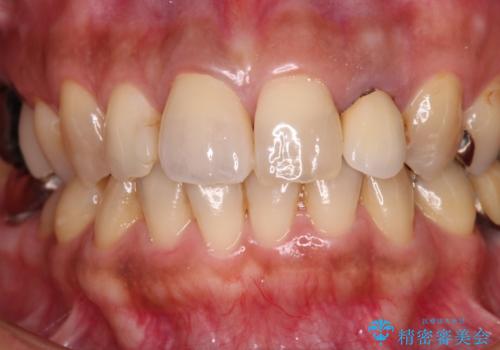

変色した保険クラウンをきれいに オールセラミッククラウンによる補綴治療

根管治療がされていなかったため、まずは根管治療を行い、その後オールセラミッククラウンにて補綴することとしました。

- 治療費の目安: 26万円(税込)費用は治療当時の料金となります